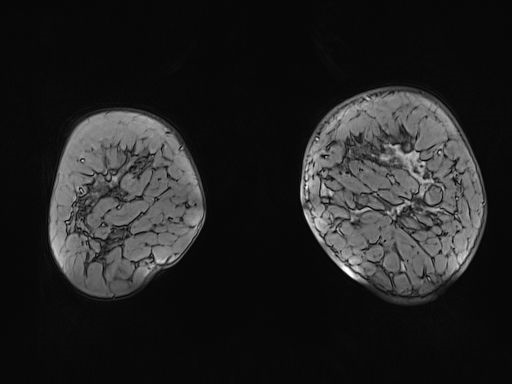

Magnetic resonance imaging (MRI) of her breast (Figures 2–4), detects diffuse pathological changes in both upper quadrants of left breast, with skin involvement at the anterior level of areola-nipple complex, approximately 90x80x65mm. There is no objective affectation of homolateral anterior pectoral muscle. Suspicious adenopathy is detected in left axillary area. It is categorised as grade 5 BIRADS lesion.

Figure 3 Magnetic resonance imaging (MRI) of the breast, detects diffuse pathological changes in both upper quadrants of the left breast.

Figure 4 Magnetic resonance imaging (MRI) of the breast with skin involvement at the anterior level and of the areola-nipple complex, of approximately 90x80x65mm.